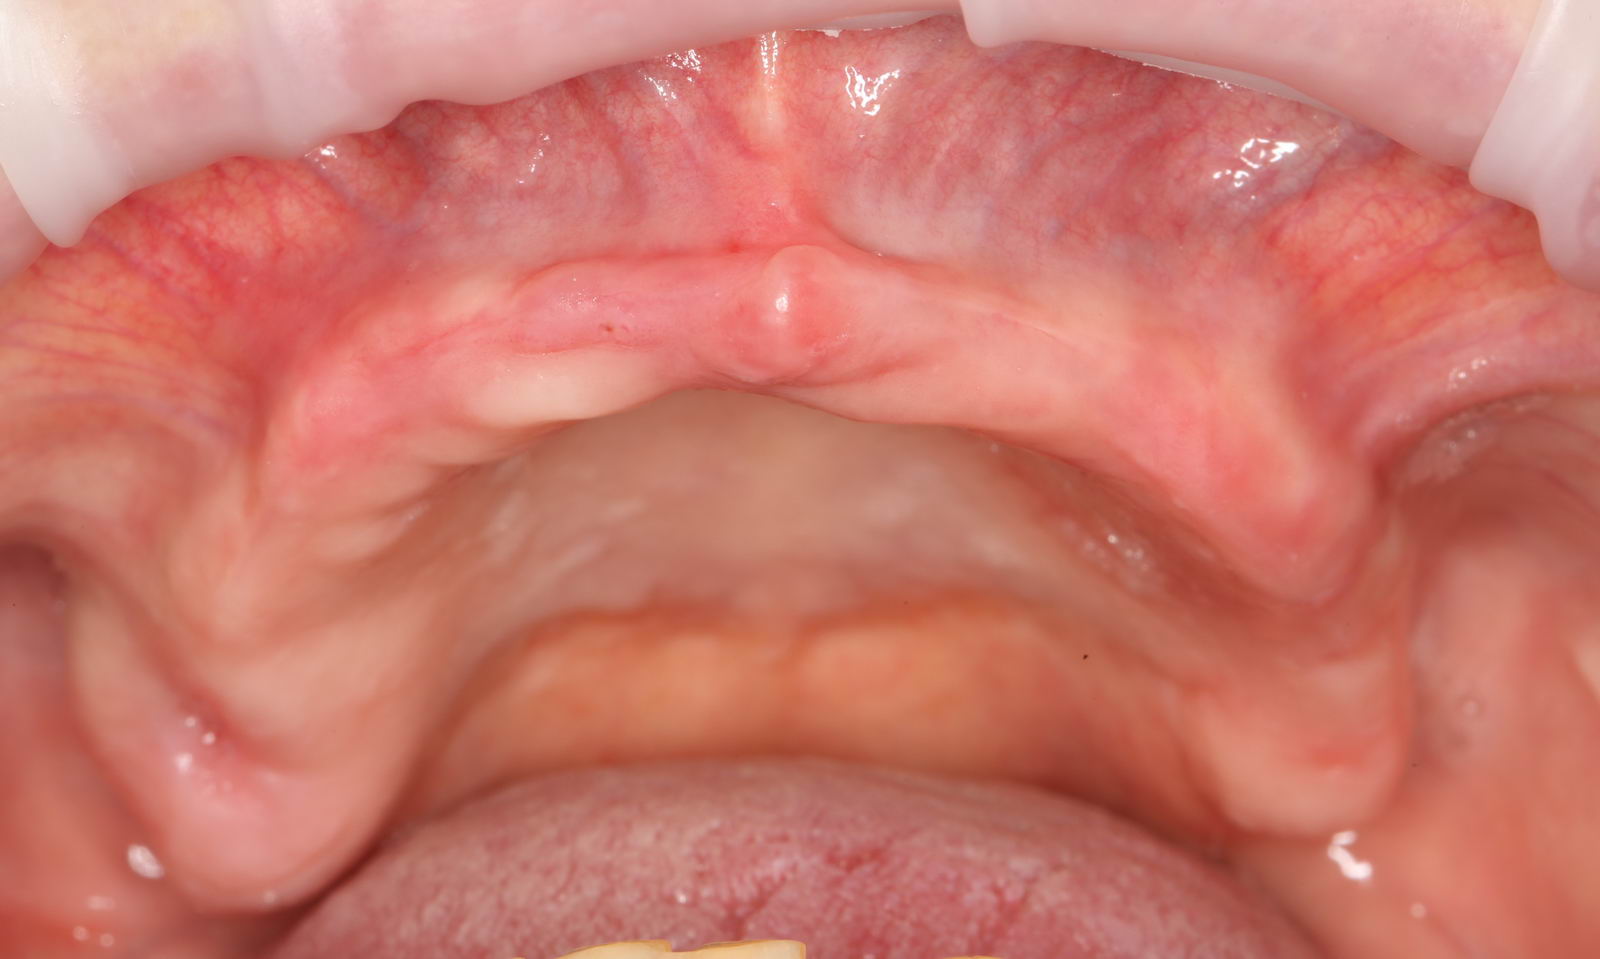

- первый пациент — это 85-летняя бабушка, которая последние тридцать лет пользовалась съемным протезом. И всё бы хорошо, но со временем, из-за атрофии челюстей, съёмный протез на одной из челюстей начал выпадать. И это даже несколько раз ставило её в неудобное положение перед соседками по даче. Вот она и обратилась к стоматологу с просьбой сделать что-нибудь, чтобы протез не вылетал.

Напомню, что 85-летнюю бабушку беспокоит то, что у неё съёмный протез выпадает. С учётом её возраста и состояния здоровья, её необходимо простое и наименее травматичное решение. Поэтому мы поставим бабушке два имплантата со специальными замками, к которым будет фиксироваться съёмный протез.

И всё! Протез не выпадает, бабушка счастлива!

Тут есть еще один бонус. Поскольку протез теперь держится за счёт имплантатов, а не «вакуума», мы можем убрать пластик с нёба и значительно уменьшить его размер. Сам протез перестал болтаться, стал более удобным. Бабушка счастлива вдвойне!